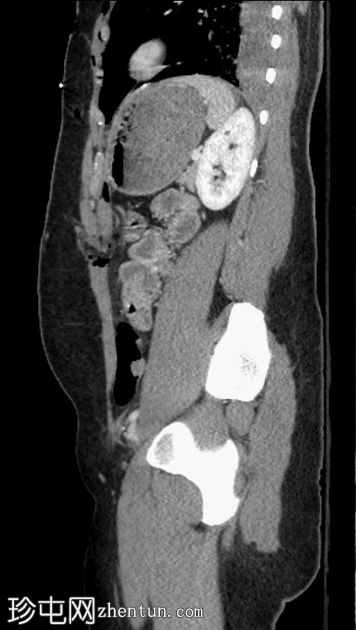

矢状位增强扫描(门静脉期)

气腹伴复杂性腹膜积液,提示全层肠损伤。

前腹壁多处刺伤,横结肠和肠系膜经右侧和左侧腹直肌鞘中部疝出。

左侧后方分层血胸。